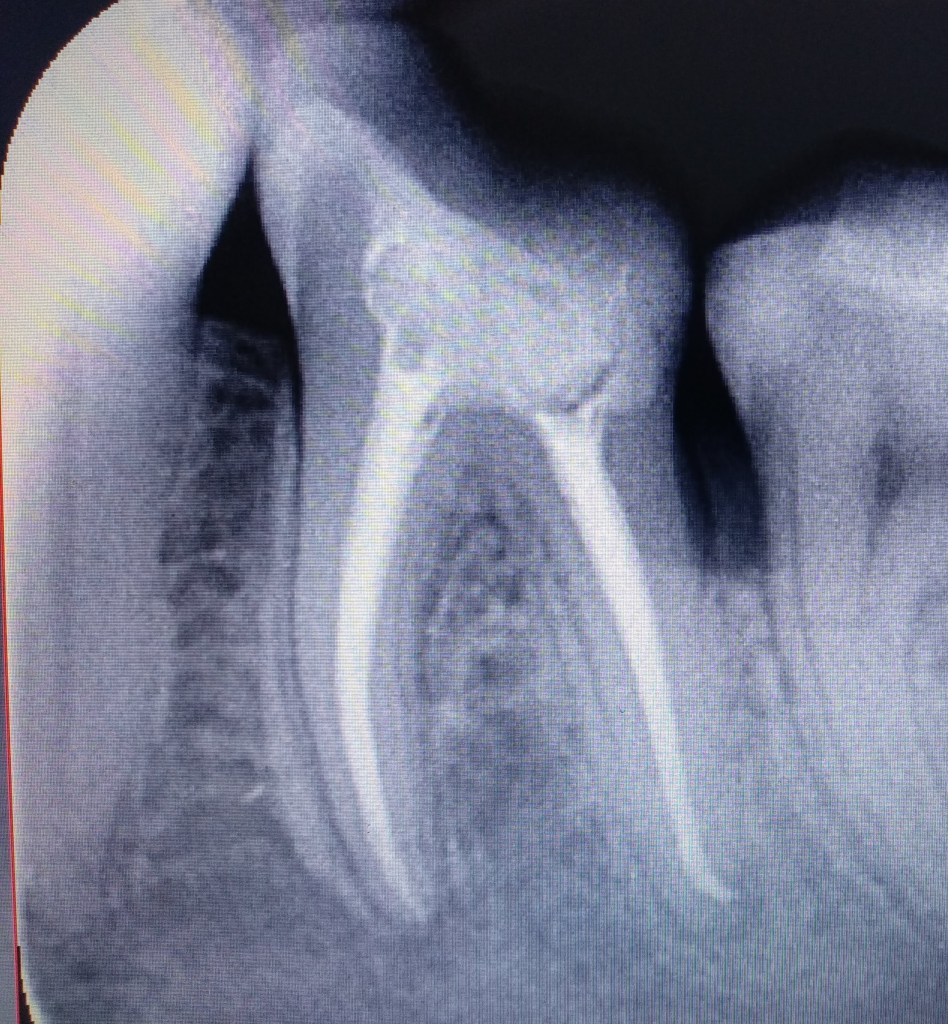

Gyökértömés cseréje: pontatlan (nem csúcsig érő, nem falálló) gyökértömések cseréje

Megmunkálás: gépi gyökércsatorna tágító (Reciproc)

Munkahossz meghatározása: apex locator (EndoPilot).

Nagyítás típusa: operációs mikroszkóp (25×)